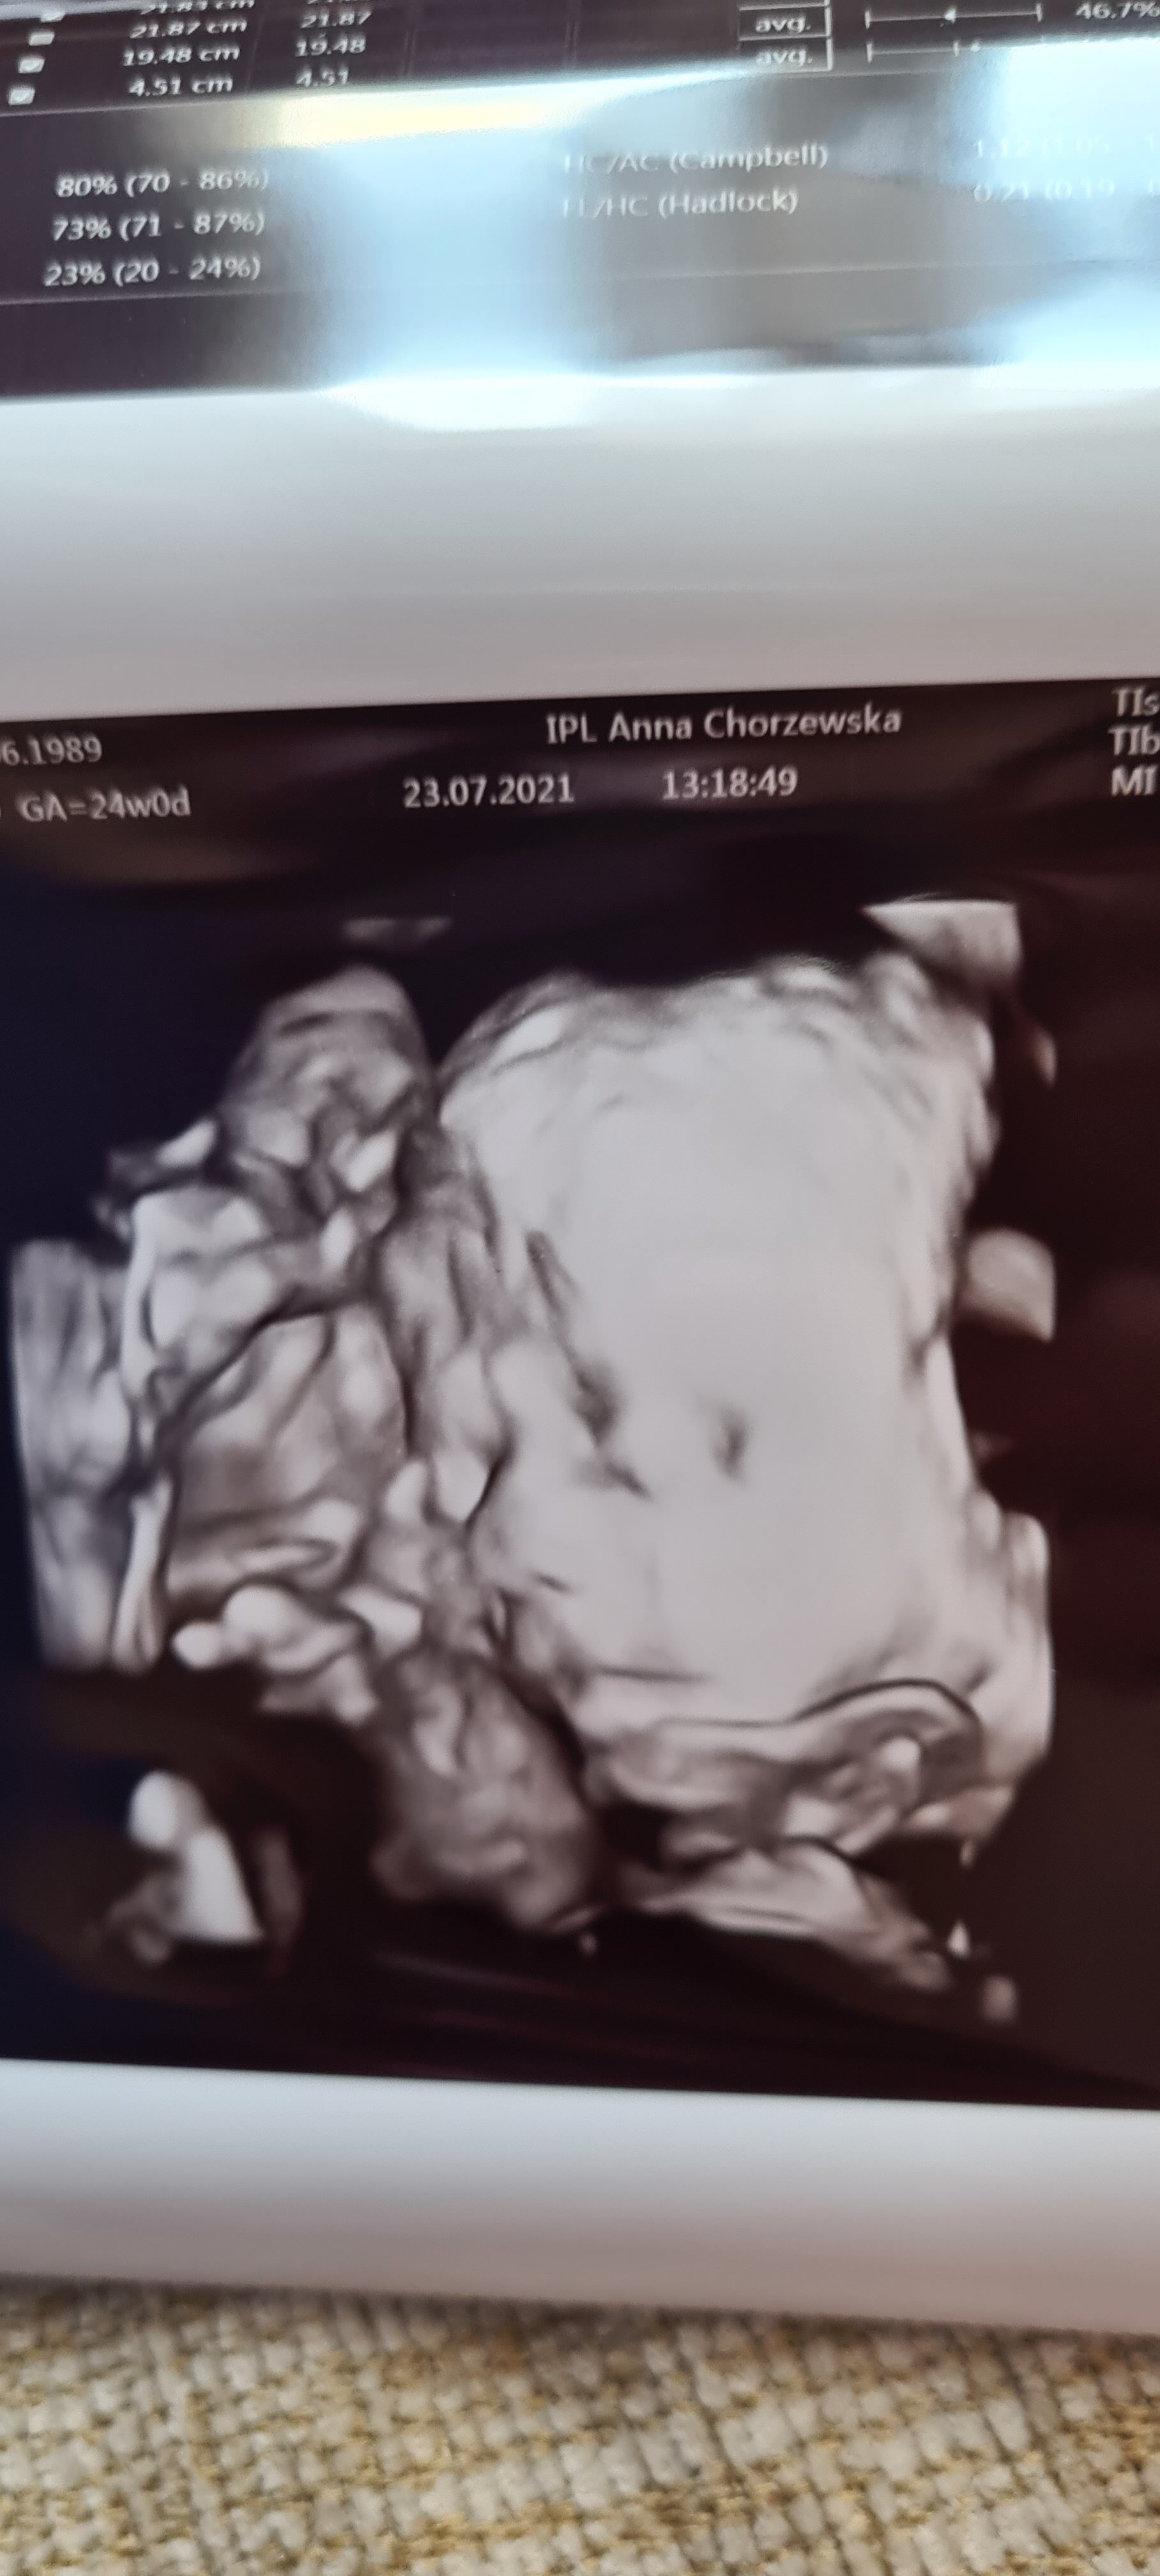

moje samopoczucie już dużo lepiej, mam nadzieję, że to się utrzyma bo te doły mnie wykańczają... Wizytę mamy 2 sierpnia, dziś jestem 21+6, ciekawe ile waży maluch i ile mierzy

widziałam filmik, który któraś z Was wrzucała o wczesniaczku z 24 tygodnia, ależ się wzruszyłam! Moja córa też, mówi "o Boże, to naprawdę już człowiek prawdziwy tam jest!"